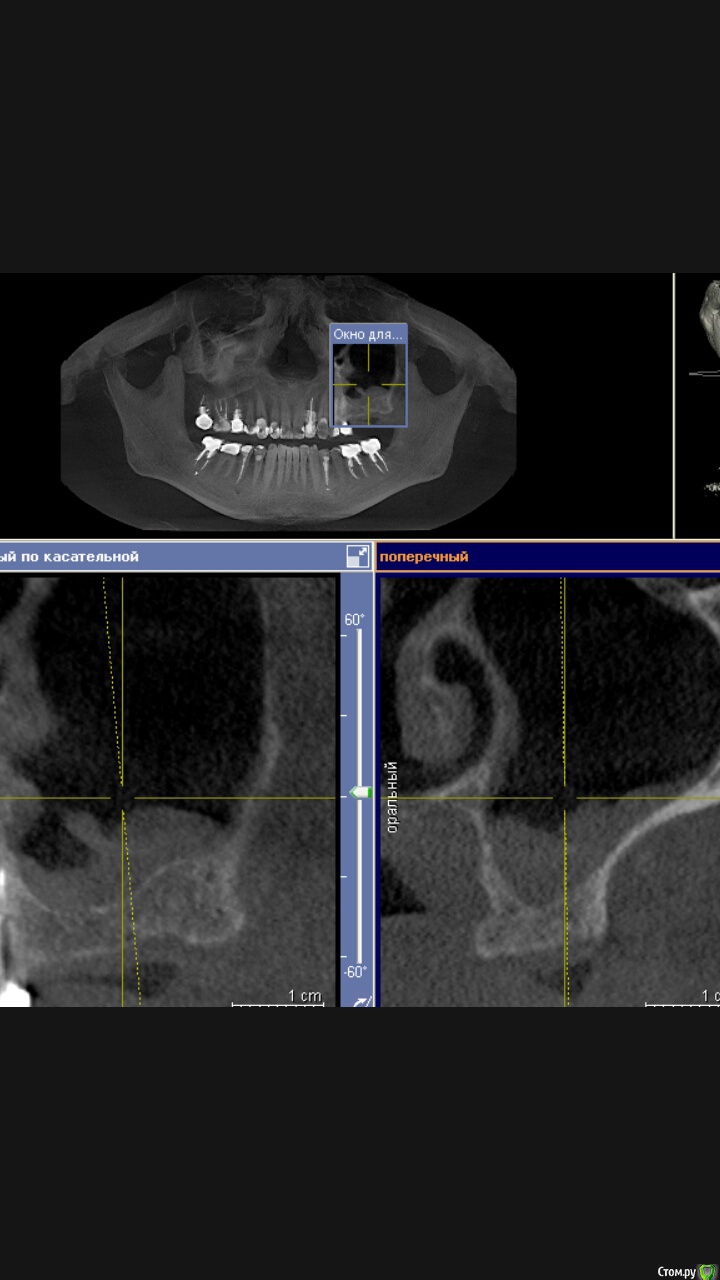

Доктор Добрых Дел Опубликовано 7 сентября, 2015 Поделиться Опубликовано 7 сентября, 2015 (изменено) У пациента была обнаружена киста в пазухе, направлен к ЛОРу. Киста удалена. Прошло полтора месяца. На КТ выглядит пазуха вот так:Вопрос - стоит ли сейчас делать синус лифтинг или нужно ещё подождать?И какие вообще мнения относительно проведения синус лифтинга при наличии подобных изменений в пазухе. Изменено 7 сентября, 2015 пользователем Доктор Добрых Дел Ссылка на комментарий

major Опубликовано 7 сентября, 2015 Поделиться Опубликовано 7 сентября, 2015 У пациента была обнаружена киста в пазухе, направлен к ЛОРу. Киста удалена. Прошло полтора месяца. На КТ выглядит пазуха вот так:Вопрос- стоит ли делать синус лифтинг или ещё подождать?И какие вообще мнения на счёт проведения синус лифтинга при наличии подобных изменений.Screenshot_2015-09-07-12-44-29.jpegСами лоры просят 4 месяца не трогать, после таких операций пристеночное утолщение до 5-7мм через 4 мес. считают приемлимым для синус-лифтинга Ссылка на комментарий

Доктор Добрых Дел Опубликовано 7 сентября, 2015 Автор Поделиться Опубликовано 7 сентября, 2015 Сами лоры просят 4 месяца не трогать, после таких операций пристеночное утолщение до 5-7мм через 4 мес. считают приемлимым для синус-лифтингаСпасибо Ссылка на комментарий